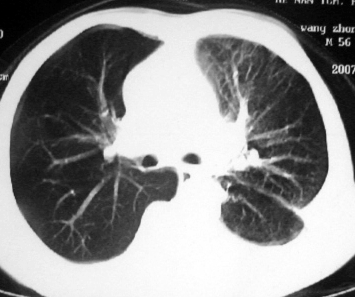

男,54岁,咳嗽,气喘半年,胸痛一月.

血性胸水

左侧胸腔积液 斜裂积液 心包积液 左肺不张 考虑左肺ca并胸膜心包转移。

支持左肺下叶中心型肺癌(累及舌叶)伴阻塞性肺炎、膨胀不全、胸腔积液、心包少量积液。

考虑左肺下叶中央型肺癌伴阻塞性肺炎及肺不张,纵隔受累可能,胸膜转移。